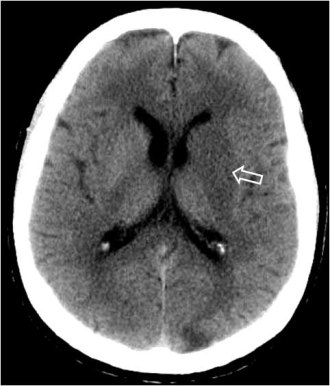

Signo visible en la TC craneal sin contraste. Fue inicialmente descrito por D.H. Yock en 1981 y corresponde a la alta densidad de la primera porción de la arteria cerebral media (ACM) comparada con la arteria contralateral, y es un signo de isquemia cerebral por oclusión arterial por trombo o émbolo, cuya densidad (80 UH=unidades Hounsfield) es más alta que la de la sangre circulante(40 UH) por la mayor cantidad de fibrina y proteínas y la menor proporción de suero.

Es un signo precoz de accidente cerebro-vascular (ACV), aparece en las primeras 6 horas y deja de verse en el ACV evolucionado, por la resolución del trombo.

Este signo tiene casi un 100 % de sensibilidad pero solo un 30 % de especificidad.

Se ha visto, como falso positivo, en pacientes asintomáticos con poliglobulia o deshidratación, por el aumento del hematocrito, aunque en este caso es bilateral. En pacientes con arteriosclerosis y calcificaciones vasculares, la apariencia de la ACM puede parecer hiperdensa. También se ha descrito en algún paciente con encefalitis por herpes simplex, que característicamente afecta al lóbulo temporal.

Imagen del mismo paciente 2 días después del primer estudio. Se observan un área hipodensa por infarto en el territorio de la ACM derecha.